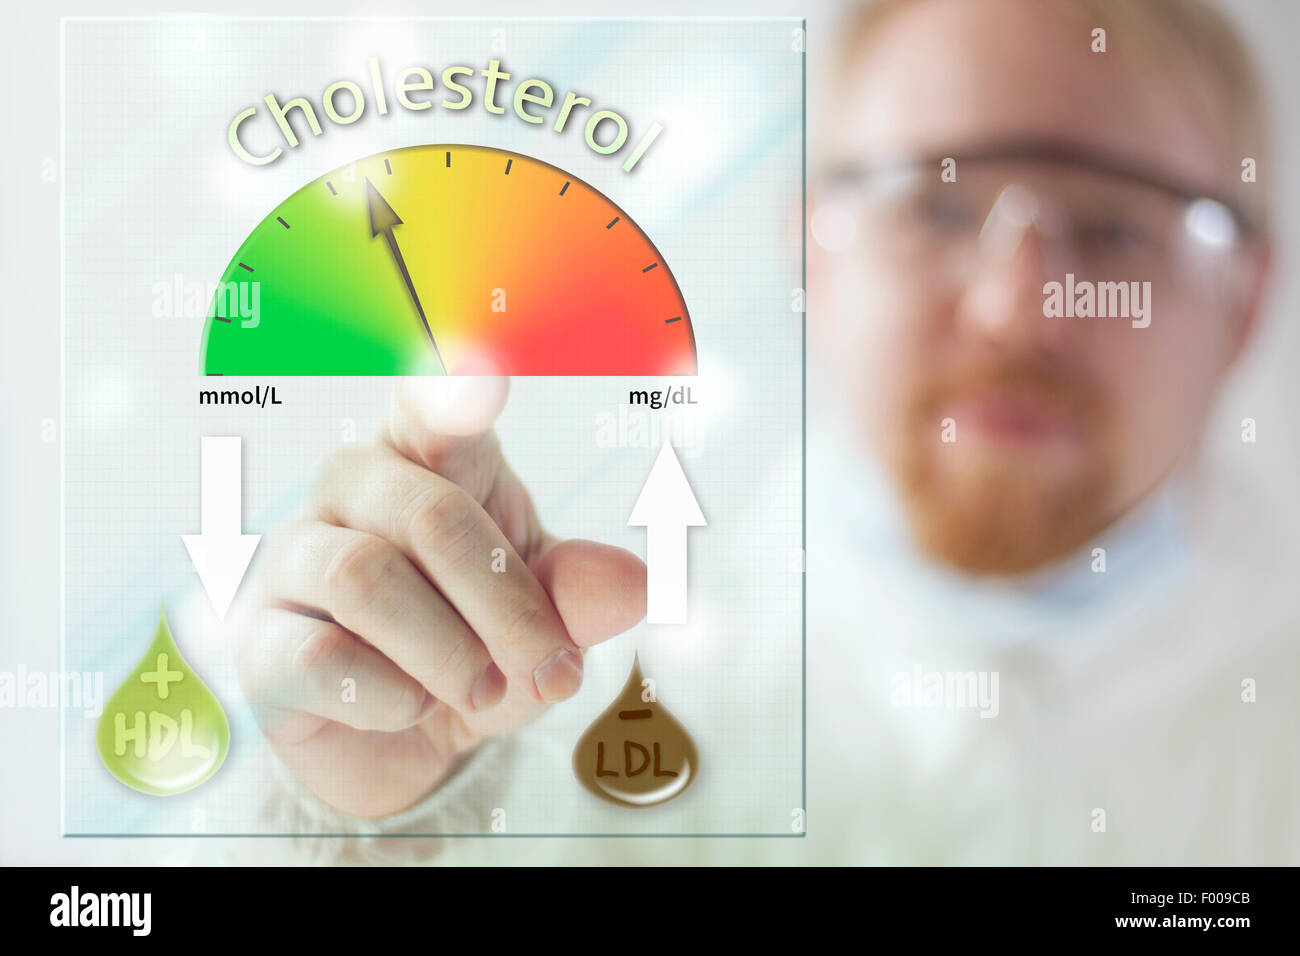

Physician and Cholesterol Level Meter at Screen Stock Photohttps://www.alamy.com/image-license-details/?v=1https://www.alamy.com/stock-photo-physician-and-cholesterol-level-meter-at-screen-86059243.html

Physician and Cholesterol Level Meter at Screen Stock Photohttps://www.alamy.com/image-license-details/?v=1https://www.alamy.com/stock-photo-physician-and-cholesterol-level-meter-at-screen-86059243.htmlRFF009CB–Physician and Cholesterol Level Meter at Screen